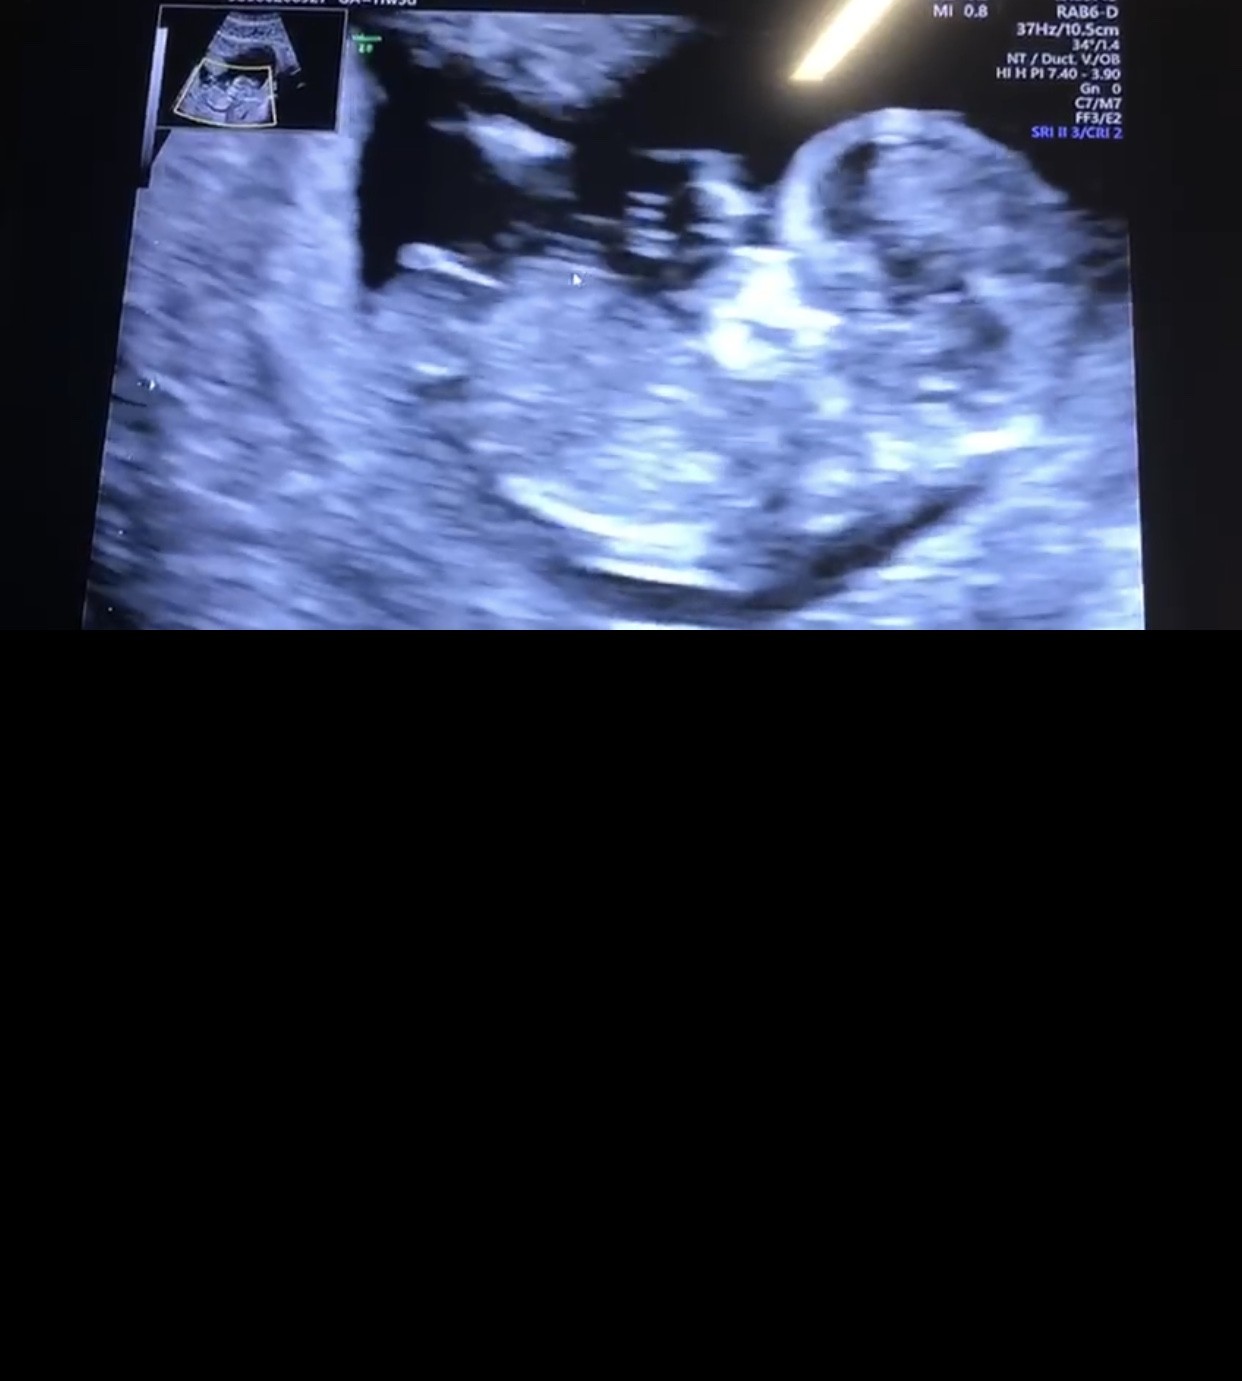

Jak myślice chłopczyk czy dziewczynka :) ?

Piękne zdjęcie ale nie pomogę ;*